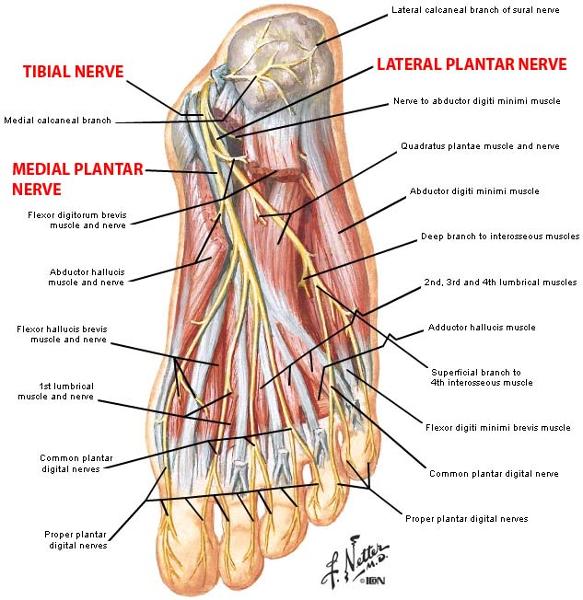

What is the pathway of the tibial nerve?

runs through popliteal fossa

runs with tom dick AN harry though medial malleoulus

bifurcates into medial and lateral plantar nerves

Into which nerves does tibial nerve bifurcate?

medial and lateral plantar nerve

Which muscles are innervated by the medial plantar nerve?

abductor hallucis and flexor digitorum brevis

1 medial lumbrical

flexor hallucis brevis

Which muscles are innervated by lateral plantar nerve in the first layer of dorsal surface?

abductor digiti minimi

origin and distribution of tibial nerve

O sciatic nerve

C forms as sciatic nerve bifurcates at apex of popliteal fossa; descends through popliteal fossa; runs inferior to tibialis posterior with posterior tibial vessels; terminates beneath flexor retinaculum by dividing into medial and lateral plantar nerves

D supplies plantar flexor muscles of the posterior compartment of the leg and knee joint

origin and distribution of lateral plantar nerve

O tibial nerve beneath flexor retinaculum

D abductor digiti minimi muscle (foot), flexor digiti minimi brevis muscle (foot), quadratus plantae, 3 lateral lumbricals of the foot, adductor hallucis muscle, plantar interossei muscles, dorsal interossei muscles

origin and distribution of medial plantar nerve

O tibial nerve beneath flexor retinaculum

D abductor hallucis, the flexor digitorum brevis, the flexor hallucis brevis, and the first lumbrical

branches of lateral plantar nerve

deep branch

superficial branch

branches of medial plantar n

common plantar digital nerves --> proper plantar digital nerves